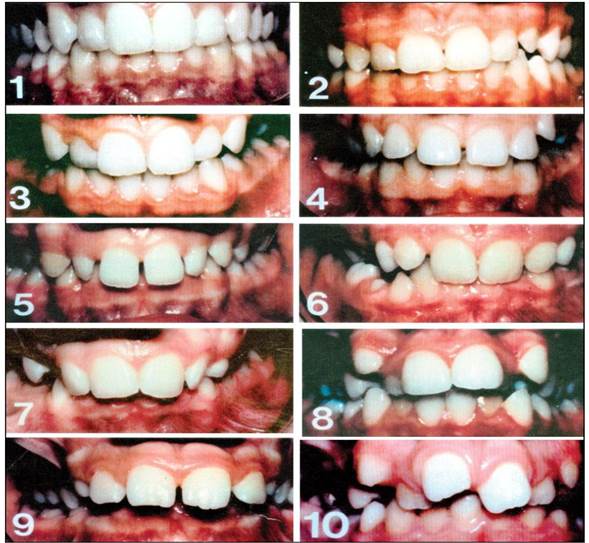

El presente estudio fue descriptivo de corte transversal, aprobado por el comité de bioética de la Universidad Andina del Cusco. La muestra estuvo constituida por 142 niños de 11 a 12 años de ambos sexos de la Institución Educativa Mariscal Gamarra, quienes reunieron los criterios de selección, el más importante que los padres hayan firmado el consentimiento informado mediante el cual se autoriza la participación del menor en la investigación, así como la participación voluntaria del escolar. A todos se les aplicó el instrumento denominado índice de Necesidad de Tratamiento de Ortodoncia (INTO). El componente estético (CE), que es de carácter subjetivo consistente en una escala análoga visual compuesta por una serie de 10 fotografías intraorales frontales que se corresponden a 10 posibles niveles estéticos dentales. Es importante aclarar que las fotografías corresponden a niños de 12 años con dentición permanente (Figura 1). La fotografía N° 1 se presenta con las características más atractivas y la fotografía N° 10 se presenta con las características menos atractivas. Este componente fue evaluado por el paciente, según su percepción, reflejando así la necesidad de tratamiento desde el punto de vista social, psicológico del tratamiento de ortodoncia. Se le pidió al niño que identifique la foto de acuerdo a la percepción de su estética dental. Si la foto que elegía se encontrara entre la 1 y la 4, se consideró sin necesidad de tratamiento; entre la 5 y 7, con necesidad moderada de tratamiento; y entre la 8 y 10, con necesidad urgente de tratamiento 5,8,9.

A través de esto se encontró que el 74,6% de los escolares percibió que no necesitaban tratamiento de ortodoncia. Esta percepción ha sido definida por el estudiante sobre su estética dental, de una serie de 10 fotografías intraorales frontales, ; este porcentaje alto se podría deber a una alta autoestima del estudiante, quien a pesar de tener una moderada necesidad de tratamiento, percibía que no necesitaba ser tratado por el Ortodoncista. En cambio los resultados que nos arroja el Componente estético, a nuestro parecer es menos confiables porque se trata de una apreciación subjetiva de un escolar de 12 años, que todavía no ha entrado a un estado de madurez emocional, que le permita ser autocrítico sobre su estética dental; son preadolescentes en quienes el desarrollo de su personalidad está en proceso. Muchos jóvenes a esta edad todavía no se preocupan mucho por su estética, a pesar de presentar un problema clínico de manifiesto.